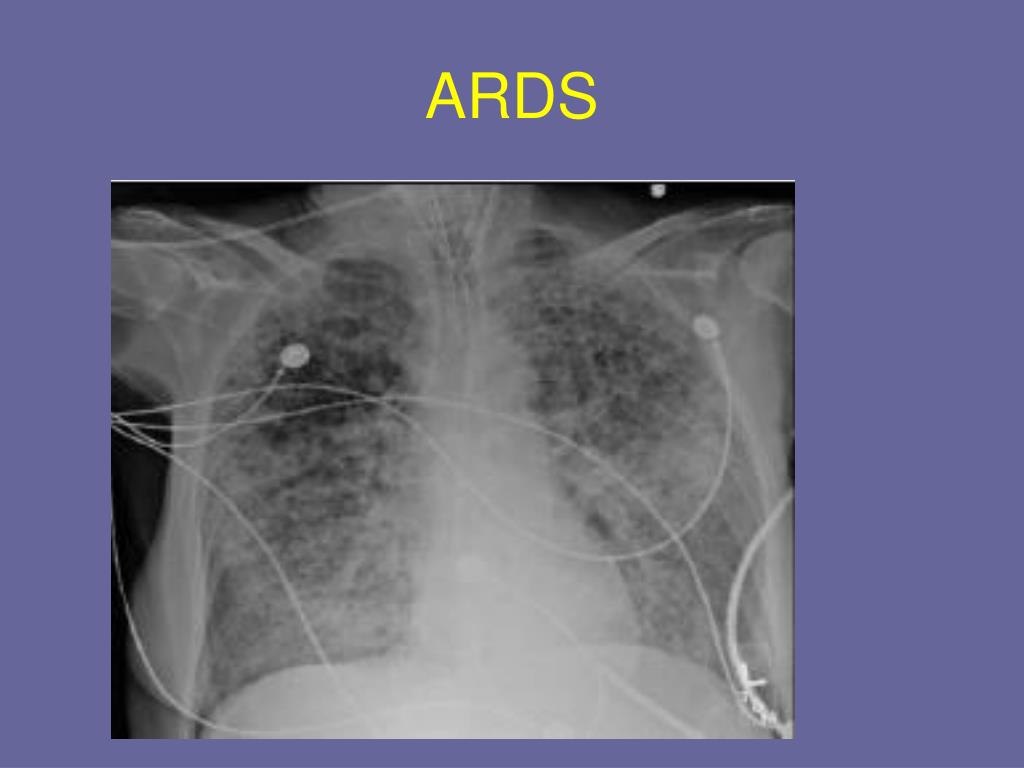

22. ARDS

15. Indications for Adult HFV • ARDS/ALI (only disease process that has been currently studied for use) • Possibly massive airleak and BP fistula